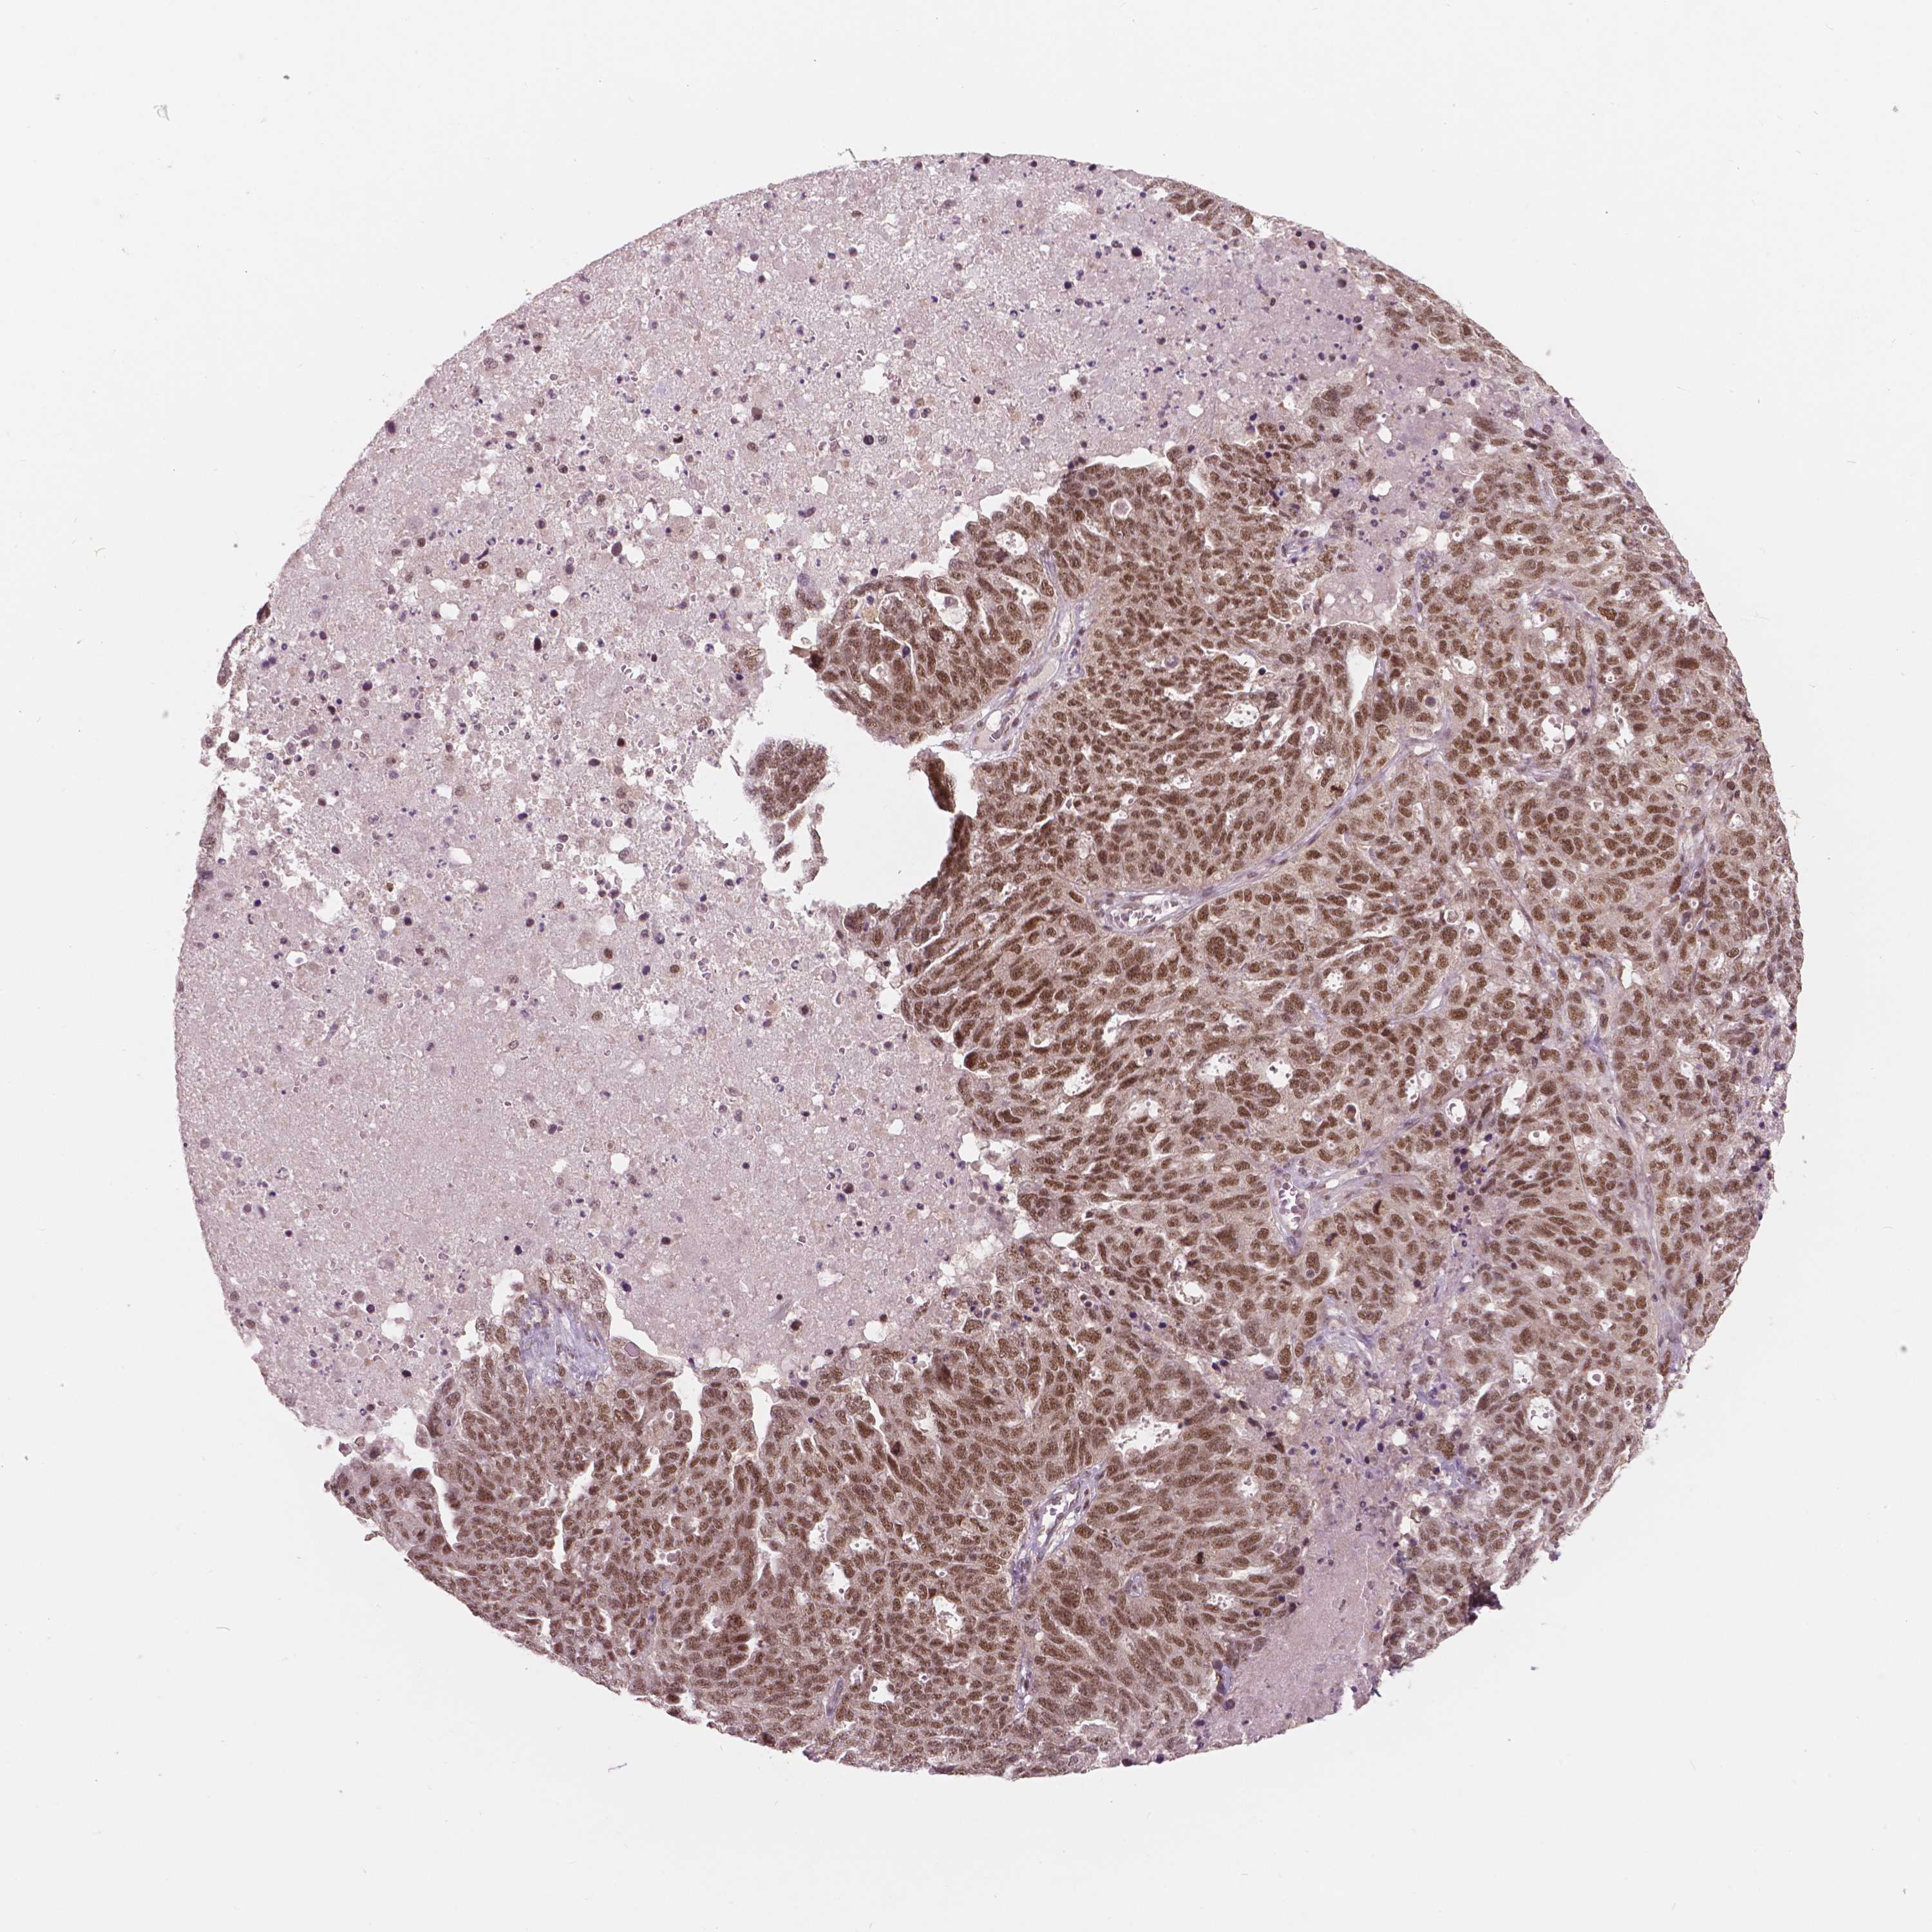

OVARIAN CANCER - Protein expressioni

A mouse-over function shows sample information and annotation data. Click on an image to view it in a full screen mode. Samples can be filtered based on level of antibody staining by selecting one or several of the following categories: high, medium, low and not detected. The assay and annotation is described here.

Note that samples used for immunohistochemistry by the Human Protein Atlas do not correspond to samples in the TCGA dataset.

Antibody stainingi

Antibody staining in the annotated cell types in the current human tissue is reported as not detected, low, medium, or high, based on conventional immunohistochemistry profiling in selected tissues. This score is based on the combination of the staining intensity and fraction of stained cells.

Each image is clickable and will lead to virtual microscopy that enables deeper exploration of all samples and also displays staining intensity scores, fraction scores and subcellular localization as well as patient and tissue information for each sample.

Antibody HPA015801

Antibody CAB068246

Antibody CAB068247

Staining

High

Medium

Low

Not detected

Intensity

Strong

Moderate

Weak

Negative

Quantity

>75%

75%-25%

<25%

None

Location

Nuclear

Cytoplasmic/membranous

Cytoplasmic/membranous,nuclear

Cystadenocarcinoma, serous, NOS

Cystadenocarcinoma, mucinous, NOS

Carcinoma, endometroid